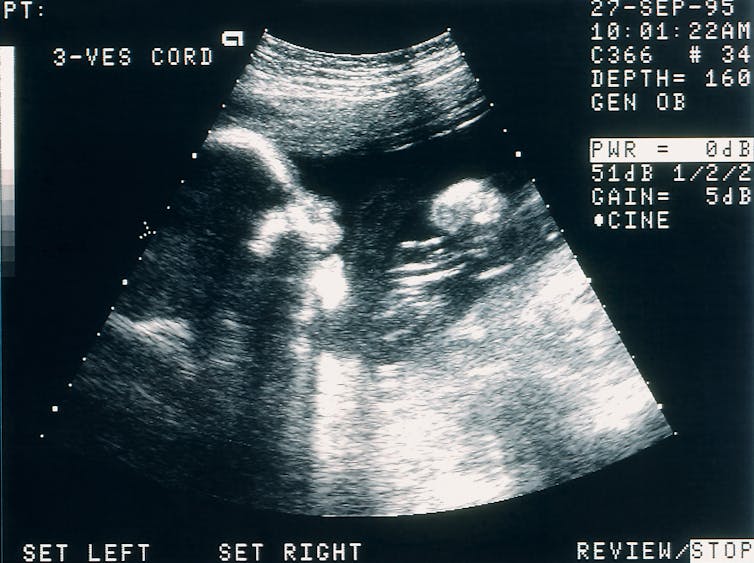

For centuries, Catholic dogma and Western legal precedent have mandated immediate cesarean section when a pregnant woman died after quickening, the point when fetal movement becomes discernible. But technological advances now make it possible sometimes for a fetus to continue gestating in place when the mother is brain-dead, or “dead by neurological criteria”– a widely accepted definition of death that first emerged in the 1950s.

The first brain death during pregnancy in which the fetus was delivered after time on life support, more accurately called organ support, occurred in 1981. The process is extraordinarily intensive and invasive, because the loss of brain function impedes many physiological processes. Health teams, sometimes numbering in the hundreds, must stabilize the bodies of “functionally decapitated” pregnant women to buy more time for fetal development. This requires vital organ support, ventilation, nutritional supplements, antibiotics and constant monitoring. Outcomes are highly uncertain.

Smith’s 112-day stint on organ support ranks third in length for a postmortem pregnancy, with the longest being 123 days. Hers is also the earliest ever gestational age from which the procedure has been attempted. Because time on organ support can vary widely, and because there is no established minimum fetal age considered too early to intervene, a fetus could theoretically be deemed viable at any point in pregnancy.